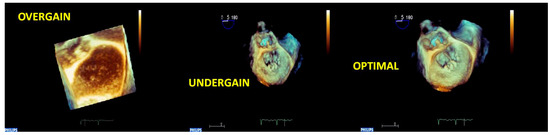

- Live RT3DE mode: Characterized by an optimal temporal resolution despite the low spatial resolution. This modality is useful to test the gain optimization.

2.3. Tips and Tricks for RT3DE Optimization